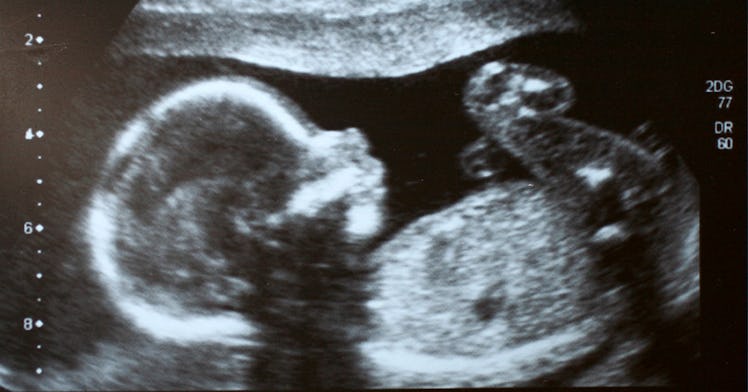

Babies Hiccup In The Womb And 6 Other Weird Facts About Fetal Behavior

Babies in the womb aren't just growing. They might even be learning.

Babies in the womb behave in ways that are startlingly similar to their behaviors outside the womb. Contrary to what some expectant parents might believe, the womb isn’t just a place where a baby grows in calm, quiet twilight isolation. Babies in the womb are busy. They poop, pee, experience sights and sounds, and practice skills they’ll use after birth, like sucking their thumb and crying. There’s even evidence babies could already be learning before coming into the world.

Plenty of parents have been delighted and surprised after high definition ultrasounds reveal their unborn baby with their thumb in the gob. There’s nothing to suggest that thumb sucking in the womb is conscious behavior. However, when you combine the ability to move arms and legs, a developing sucking reflex, and cramped quarters, it makes sense that should the thumb bump into mouth, it will be sucked.